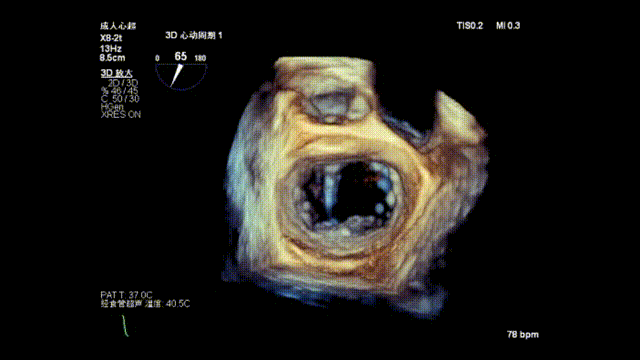

确定瓣膜夹与病变区域垂直后,放下夹片,超声确认前叶后叶都夹合充分,3D检查瓣膜夹位置.

前瓣超声测量抓取1.00cm,后瓣抓捕1.04cm,抓捕充分;

瓣膜夹释放前评估发现返流改善明显,仅存少量返流。